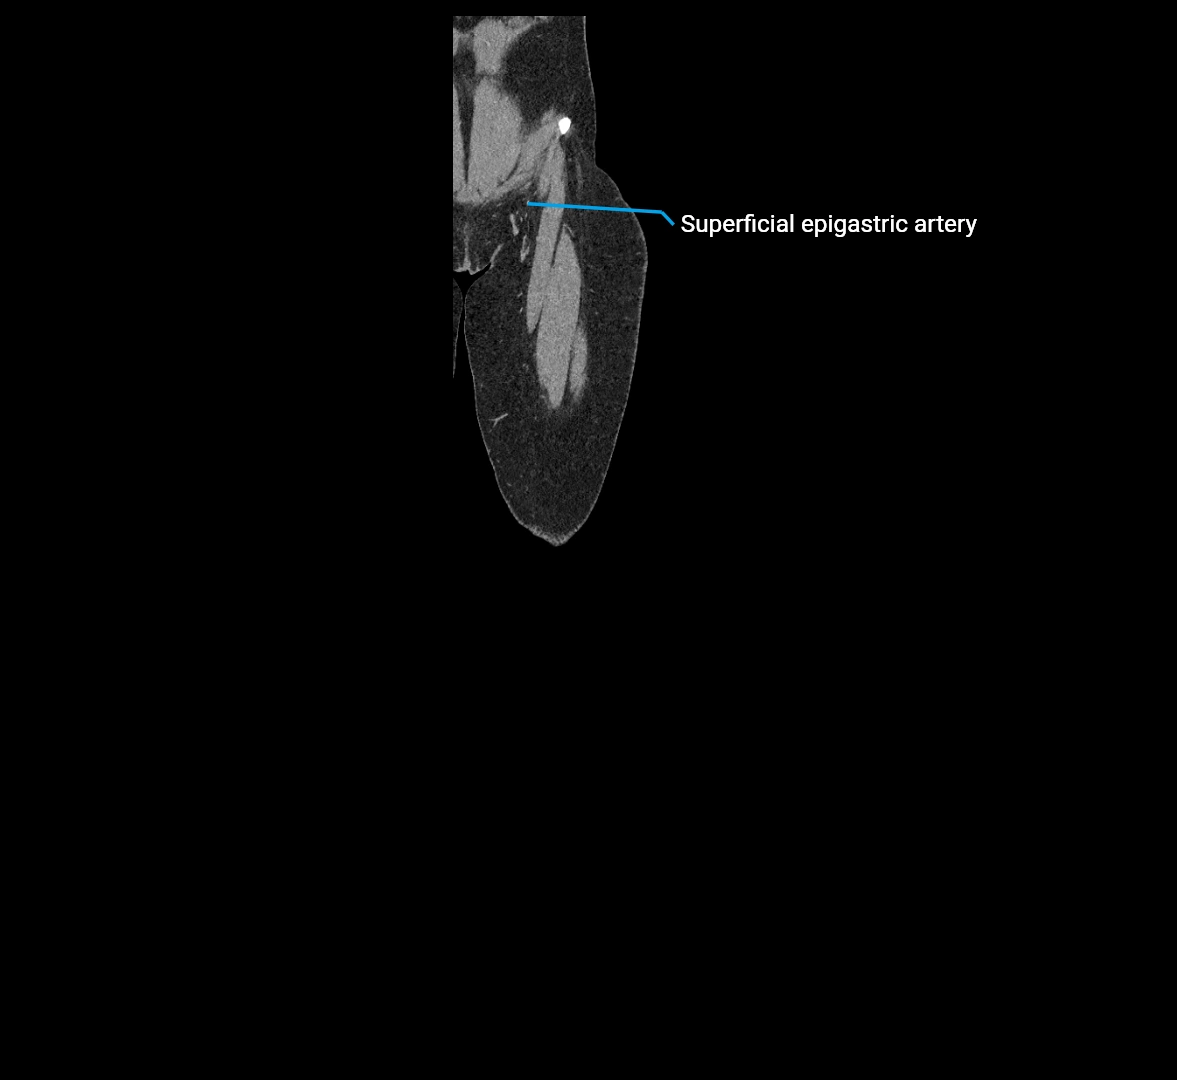

CT images

image